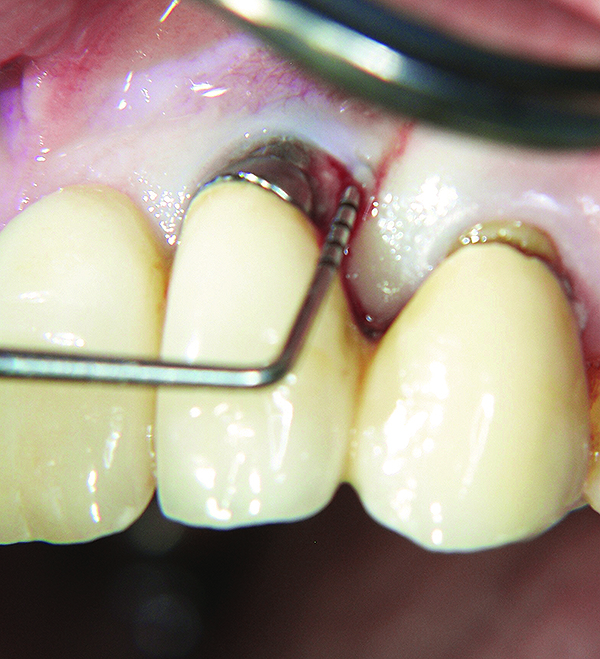

The presence of keratinized tissue around teeth and implants and its role in periodontal maintenance is somewhat controversial. It has been suggested that 2 mm of keratinized tissue is important to maintain gingival health around teeth.16 Minimal recession also facilitates maintenance by the therapist and plaque control by the patient (Figure 4 and Figure 5). Keratinized tissue around implants is also important. Chung et al17 completed a retrospective study examining the barrier function of keratinized tissue around dental implants. They examined 339 endosseous dental implants in place for at least 3 years in 69 patients and found that when an adequate band of keratinized tissue was present, less inflammation and plaque accumulation occurred (Figure 6 and Figure 7). Although there was no correlation to bone loss, there was improved comfort while cleaning the sites with keratinized tissue versus those areas that lacked keratinized tissue.

Fig 7. Close-up view of the No. 23 implant-supported restoration showing inflammation surrounding the site (this area had not been grafted).

Figure 7

Fig 8. The implant on No. 23 4 years later with no maintenance care, showing increased inflammation and recession.

Figure 8